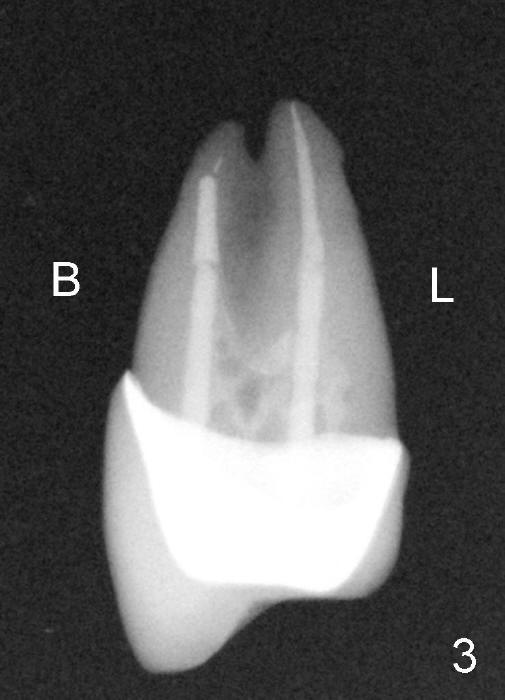

A 50-year-old man has mild pain in the upper left 1st bicuspid 3 years after root canal retreatment with placement of two posts (Fig.1). Findings of clinical exam are consistent with root fracture (Fig.2). Extraction reveals two fused roots (Fig.3,4). Probing indicates that the buccal plate is defective. Osteotomy is initiated in the palatal socket with a 2 mm pilot drill, followed by 2.5 and 3.0 mm reamers and 4.5x20 mm tap. The septum appears to have been pushed buccally (Fig.5 *) and form a new buccal wall (partially, strengthened by bone graft mentioned below) for the implant to be placed. The implant (4.5x20 mm) is placed in the palatal socket (Fig.6 *) with insertion of an abutment (A: 3.5x5 mm 0º), while a mixture of autogenous bone (harvested from reamers) and Synthograft (Bicon) is placed in the shrunken buccal socket (Fig.7; using allograft may decrease postop bony shrinkage). The bone graft is then contained by an immediate provisonal without collagen membrane or flaps. The patient is doing well postop. The gingiva is healthy (Fig.8*) when the provisional is removed 3 months postop with normal papillae (Fig.9 arrowheads). It remains the same 1 month post cementation (Fig.10,11). For further follow up, see immediate implant of the tooth #13.